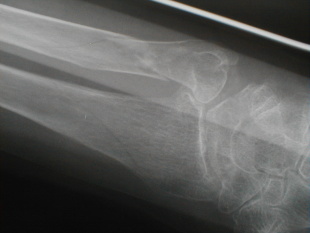

右前腕骨骨折

負傷日時 平成13年11月26日

自宅寝室からトイレに行きしなに、廊下で転倒した際に手をつき負傷

受傷時撮影1 受傷時撮影2